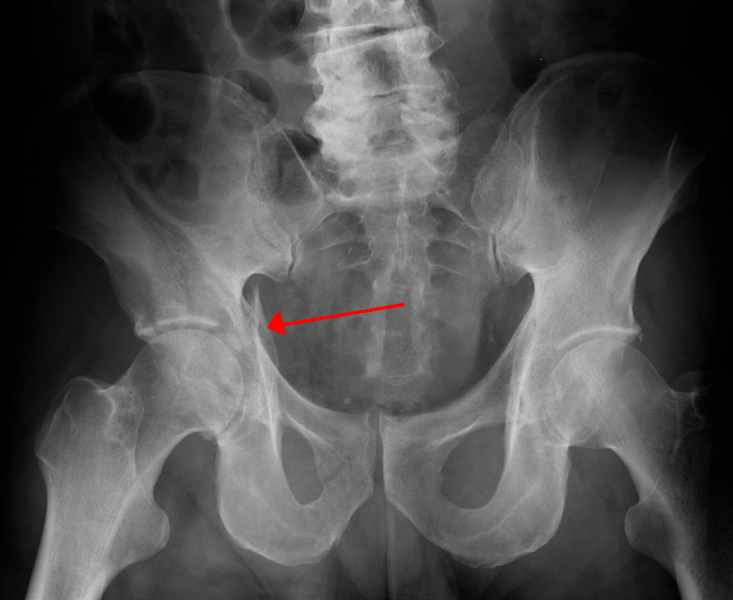

- Iliopubic line extends from ilium to superior pubic ramus

- Ilioischial line- extends from ilium to ischial ramus forming radiographic teardrop, "U" shaped, on AP pelvis

- Quadrilateral plate forms medial wall of acetabulum